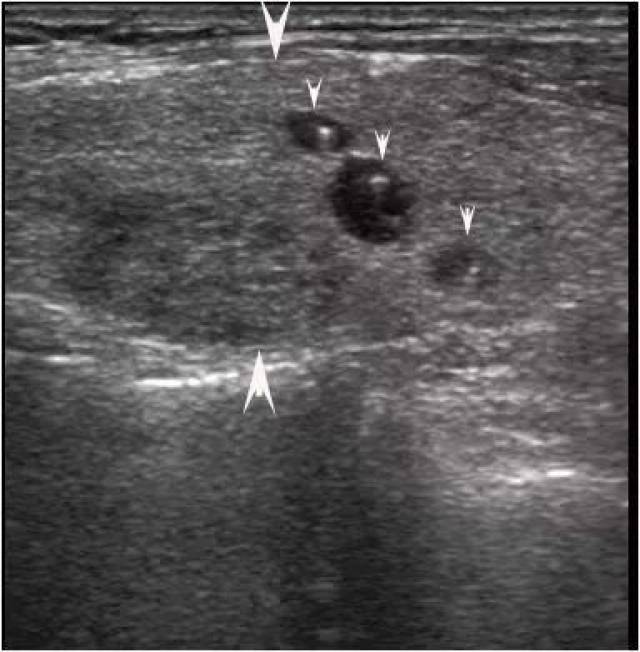

胶质潴留、钙化?教你正确解读甲状腺超声的7种常见影像

答:根据超声表现可把甲状腺结节恶性危险分为五级. I级:形状规整的圆形或椭圆形无回声结 腺瘤性结节. III级:形状规整的均匀实性回声结节,有时在被膜或结节内可见到微钙化,内部